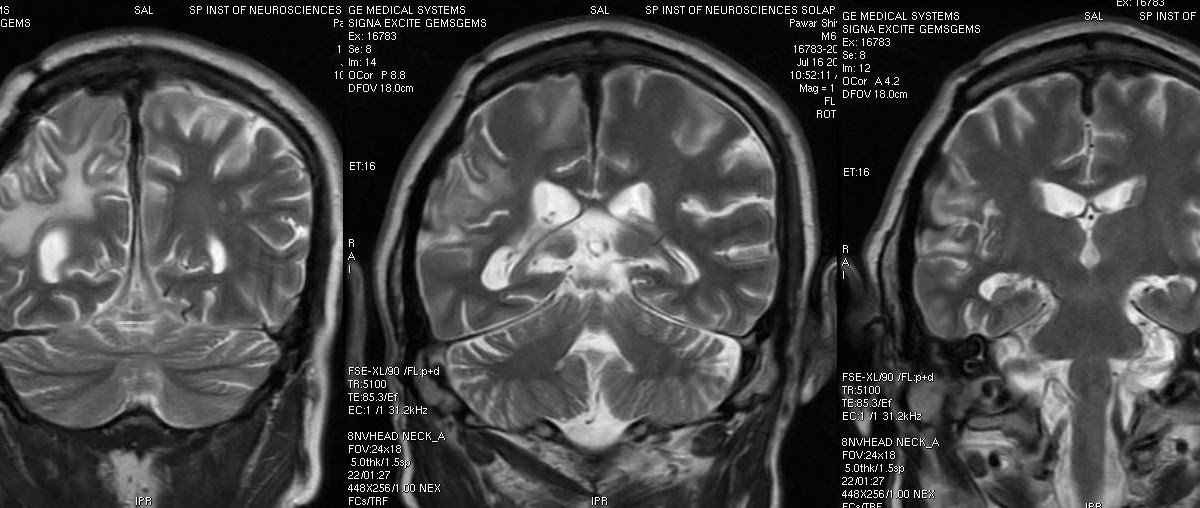

Diagnostic Neuroradiology

Dr Balaji Anvekar U0026 39 S Neuroradiology Cases Hypertrophic Patchymeningitis Mri

A New Index For The Assessment Of Transverse Sinus Stenosis For Diagnosing Idiopathic

Teaching Neuroimage Mri Visualization Of Papilledema Associated With Cerebral Sinovenous

Normal Cranial Nerves In The Cavernous Sinuses Contrast

Posterior Cerebral Artery Infarct Early Subacute U2014 Clinical Mri